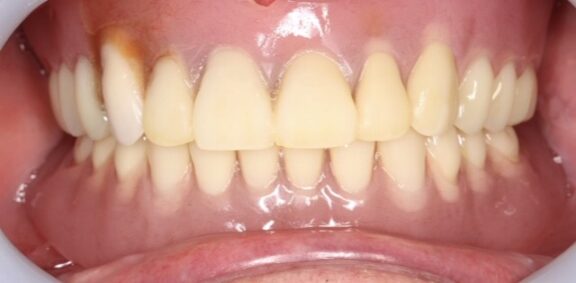

☆下の総入れ歯がゆるくて食べにくい。と言われ

当院でのインプラントオーバーデンチャーを入れた症例です。

患者様より、下の総入れ歯の気になっていたところが全て解消し

何でも噛めて、インプラントオーバーデンチャーにして本当に良かった☺️

と満面の笑みで喜んでいただけて、こちらも大変嬉しく思いました。